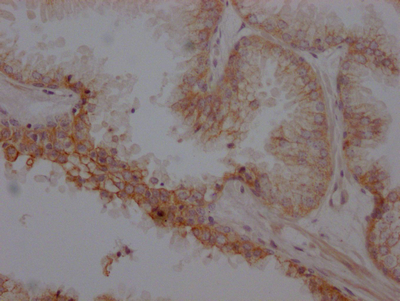

IHC (Immunohistochemistry)

(The image on the left is immunohistochemistry of paraffin-embedded Human liver cancer tissue using AAA239663(ADRB2 Antibody) at dilution 1/20, on the right is treated with synthetic peptide. (Original magnification: ×200))